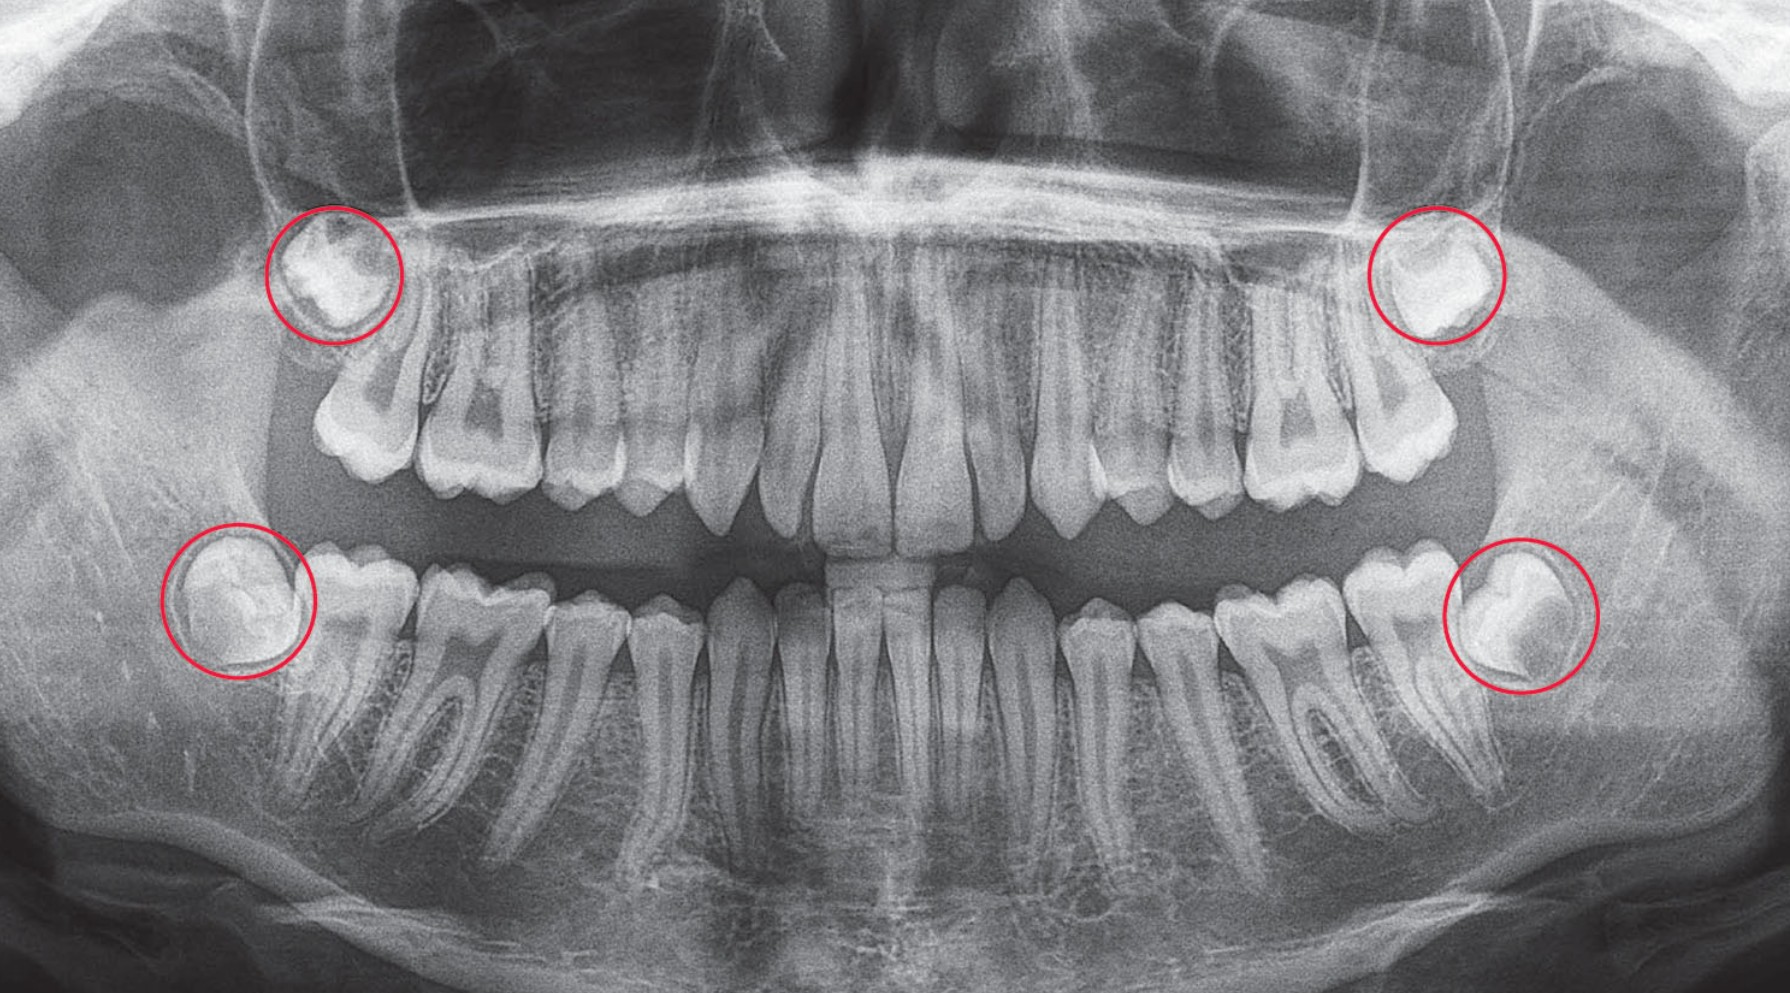

Răng khôn là chiếc răng nằm ở vị trí cuối cùng của cung hàm, sát với góc hàm dưới hoặc phía sau răng hàm trên. Đây là chiếc răng mọc sau cùng, khi các răng khác đã ổn định vị trí và xương hàm không còn nhiều chỗ trống để răng trồi lên.

Chính vì không gian mọc hạn chế, răng khôn rất dễ bị lệch, ngầm hoặc kẹt trong xương hàm. Một số trường hợp, răng chỉ mọc lên một phần rồi dừng lại, tạo thành “túi lợi trùm” – nơi thức ăn dễ mắc vào, gây viêm nhiễm và đau nhức.

- Răng khôn mọc lệch hoặc mọc ngầm: Khi răng mọc lệch, chúng có thể chèn ép răng số 7 bên cạnh, làm tổn thương chân răng hoặc gây viêm nướu quanh thân răng.

- Cần chụp X-quang răng để xác định hướng mọc của răng khôn và đánh giá có cần nhổ bỏ hay không.